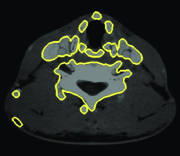

Appearance is one of the most important visual cues to distinguish between different structures in an image. Appearance is described by studying the distribution of different features such as intensity values in gray-scale images, color, and texture inside each object. In most cases, appearance models are incorporated into the data term in (2) and (7). The purpose of incorporating appearance prior is to fit the appearance distribution of the segmented objects to the distribution of objects of interest, e.g. using Gaussian mixture model (GMM) (Rother et al., 2004). In the literature, there are two ways to model the appearance: 1) adaptively learning the appearance during the segmentation procedure, and 2) knowing the appearance model prior to performing segmentation (e.g. by observing the appearance distribution of the training data). In the former case, the appearance model is learned as the segmentation is performed (Vese and Chan, 2002) (computed online). In the second case, it is assumed that the probability of each pixel belonging to particular label is known, i.e. if represents a particular set of feature values (e.g. intensity/color) associated with each image location for object, then it is assumed that is known (or pre-computed offline). This probability is usually learned and estimated from the distribution of features inside small samples of each object. Figure 9 illustrates the probability of different structures (the kidney, the tumour, and the background) in an endoscopic scene. A lower intensity in Figures 9(b-d) corresponds to higher probability.